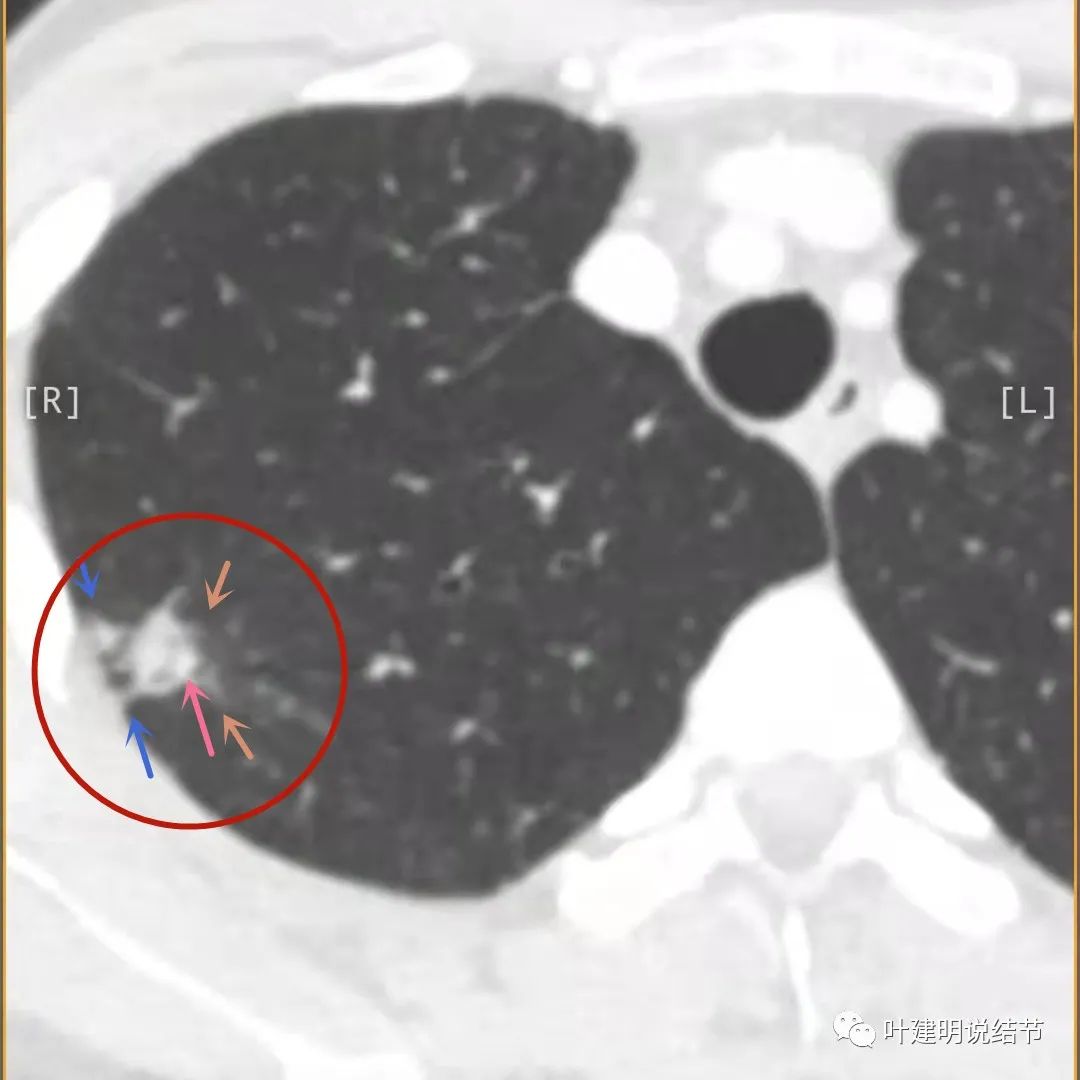

上面是她提供的病史资料,其中最重要的是PPD强阳性!其他主要看影像,我们先来看她2020年7月份的平扫片子(由于片子较多,详细展示是为了同道分析,我在影像特征描述上将只选取部分加以说明):

右肺尖偏实性结节(粉色箭头),邻近胸胸膜明显增厚不平,且广基附在胸壁上(蓝色箭头)

主病灶出现,粉色箭头示病灶密度较高,边上有磨玻璃影,甚淡(砖色箭头)

影像初印象:右上病灶散在,不致密,密度偏高,磨玻璃影不是平时典型恶性的磨玻璃瘤肺边界清楚或含毛刺征的征象,更符合炎性病变,且邻近胸膜广基的异常增厚。